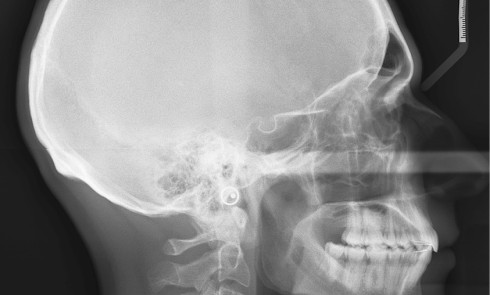

Quelles sont les 7 formes cliniques des épulis ? 1. Épulis inflammatoire (plasmocytaire) Nodule indolore, pédiculé, érythémateux, parfois ulcéré (fig. 1a)....